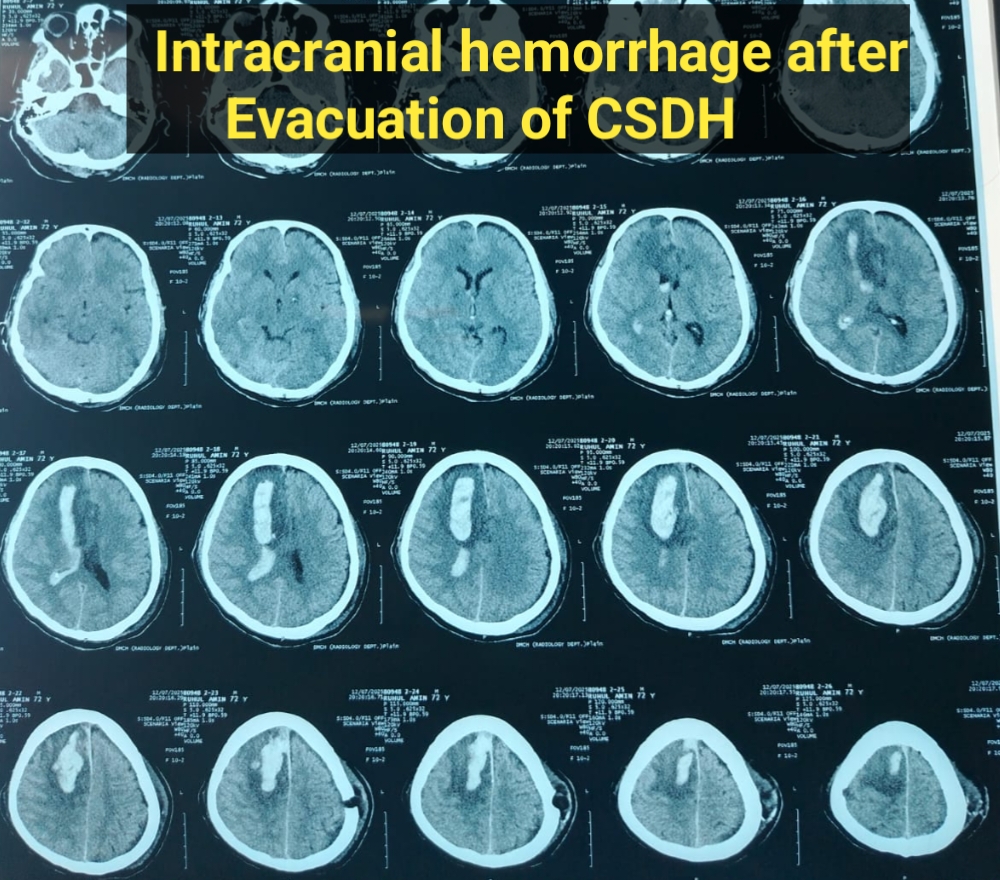

মাথা ব্যথা, ঘাড় ব্যথা, কোমর ব্যথা, পিএলআইডি সমস্যা, হেড ইনজুরি , স্পাইন ইনজুরি , স্পাইনের রড-স্ক্র ফিক্সেশন, মস্তিষ্ক - স্নায়ু - মেরুদণ্ড ব্যথা, স্পাইনাল টিউমার, ব্রেইন টিউমার, প্যারালাইসিস বা পক্ষাঘাত, স্ট্রোক, হাত - পায়ে ব্যথা, হাতে পায়ে ঝিমঝিম ভাব , শিশু নিউরোসার্জারি , ভাসকুলার নিউরোসার্জারি বিশেষজ্ঞ ও নিউরোসার্জন।